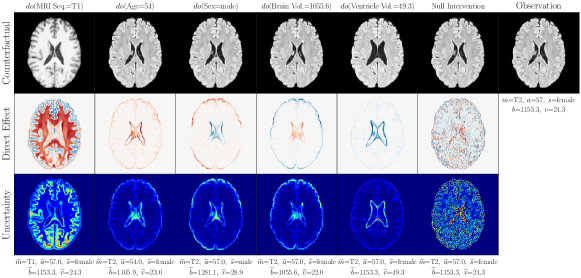

4.2 Brain Imaging Counterfactuals

To demonstrate our model’s ability to produce faithful high-fidelity counterfactuals of real data, we extend our approach to a real-world scenario involving brain MRI scans from the UK Biobank (Sudlow et al., 2015). As before, we start with an assumed causal generative process involving a set of observed variables as shown in Figure 4(a). The causal graph is medically informed and extends the scenario in Pawlowski et al. (2020) by: (i) introducing an additional MRI Sequence (T1/T2) binary variable to enable discrete counterfactuals; (ii) having directly. We used a scaled-up version of our exogenous prior HVAE as ’s mechanism and used (conditional) normalizing flows for the other mechanisms (see Appendix A.1). As shown in Figure 4, our deep SCM is capable of producing qualitatively sharp counterfactuals with localised changes according to the intervened upon parent(s) and the associated causal graph. Importantly, the identity of subjects is well preserved in all cases including null-interventions (i.e. nothing). Table 2 shows the counterfactual effectiveness results from random interventions on each variable. We observed satisfactory initial counterfactual effectiveness and significant improvements of post counterfactual training, demonstrating the merit of the proposed approach. Please refer to Appendix A.2 for notes on abduction uncertainty and D for additional results.

D.3 Extra Results

‘MRI Seq.’ counterfactuals

Post counterfactual training:

‘Sex’ counterfactuals

‘Age’ counterfactuals

‘Brain Volume’ counterfactuals

‘Ventricle Volume’ counterfactuals

Random Samples from full SCM

Null-Interventions on full SCM